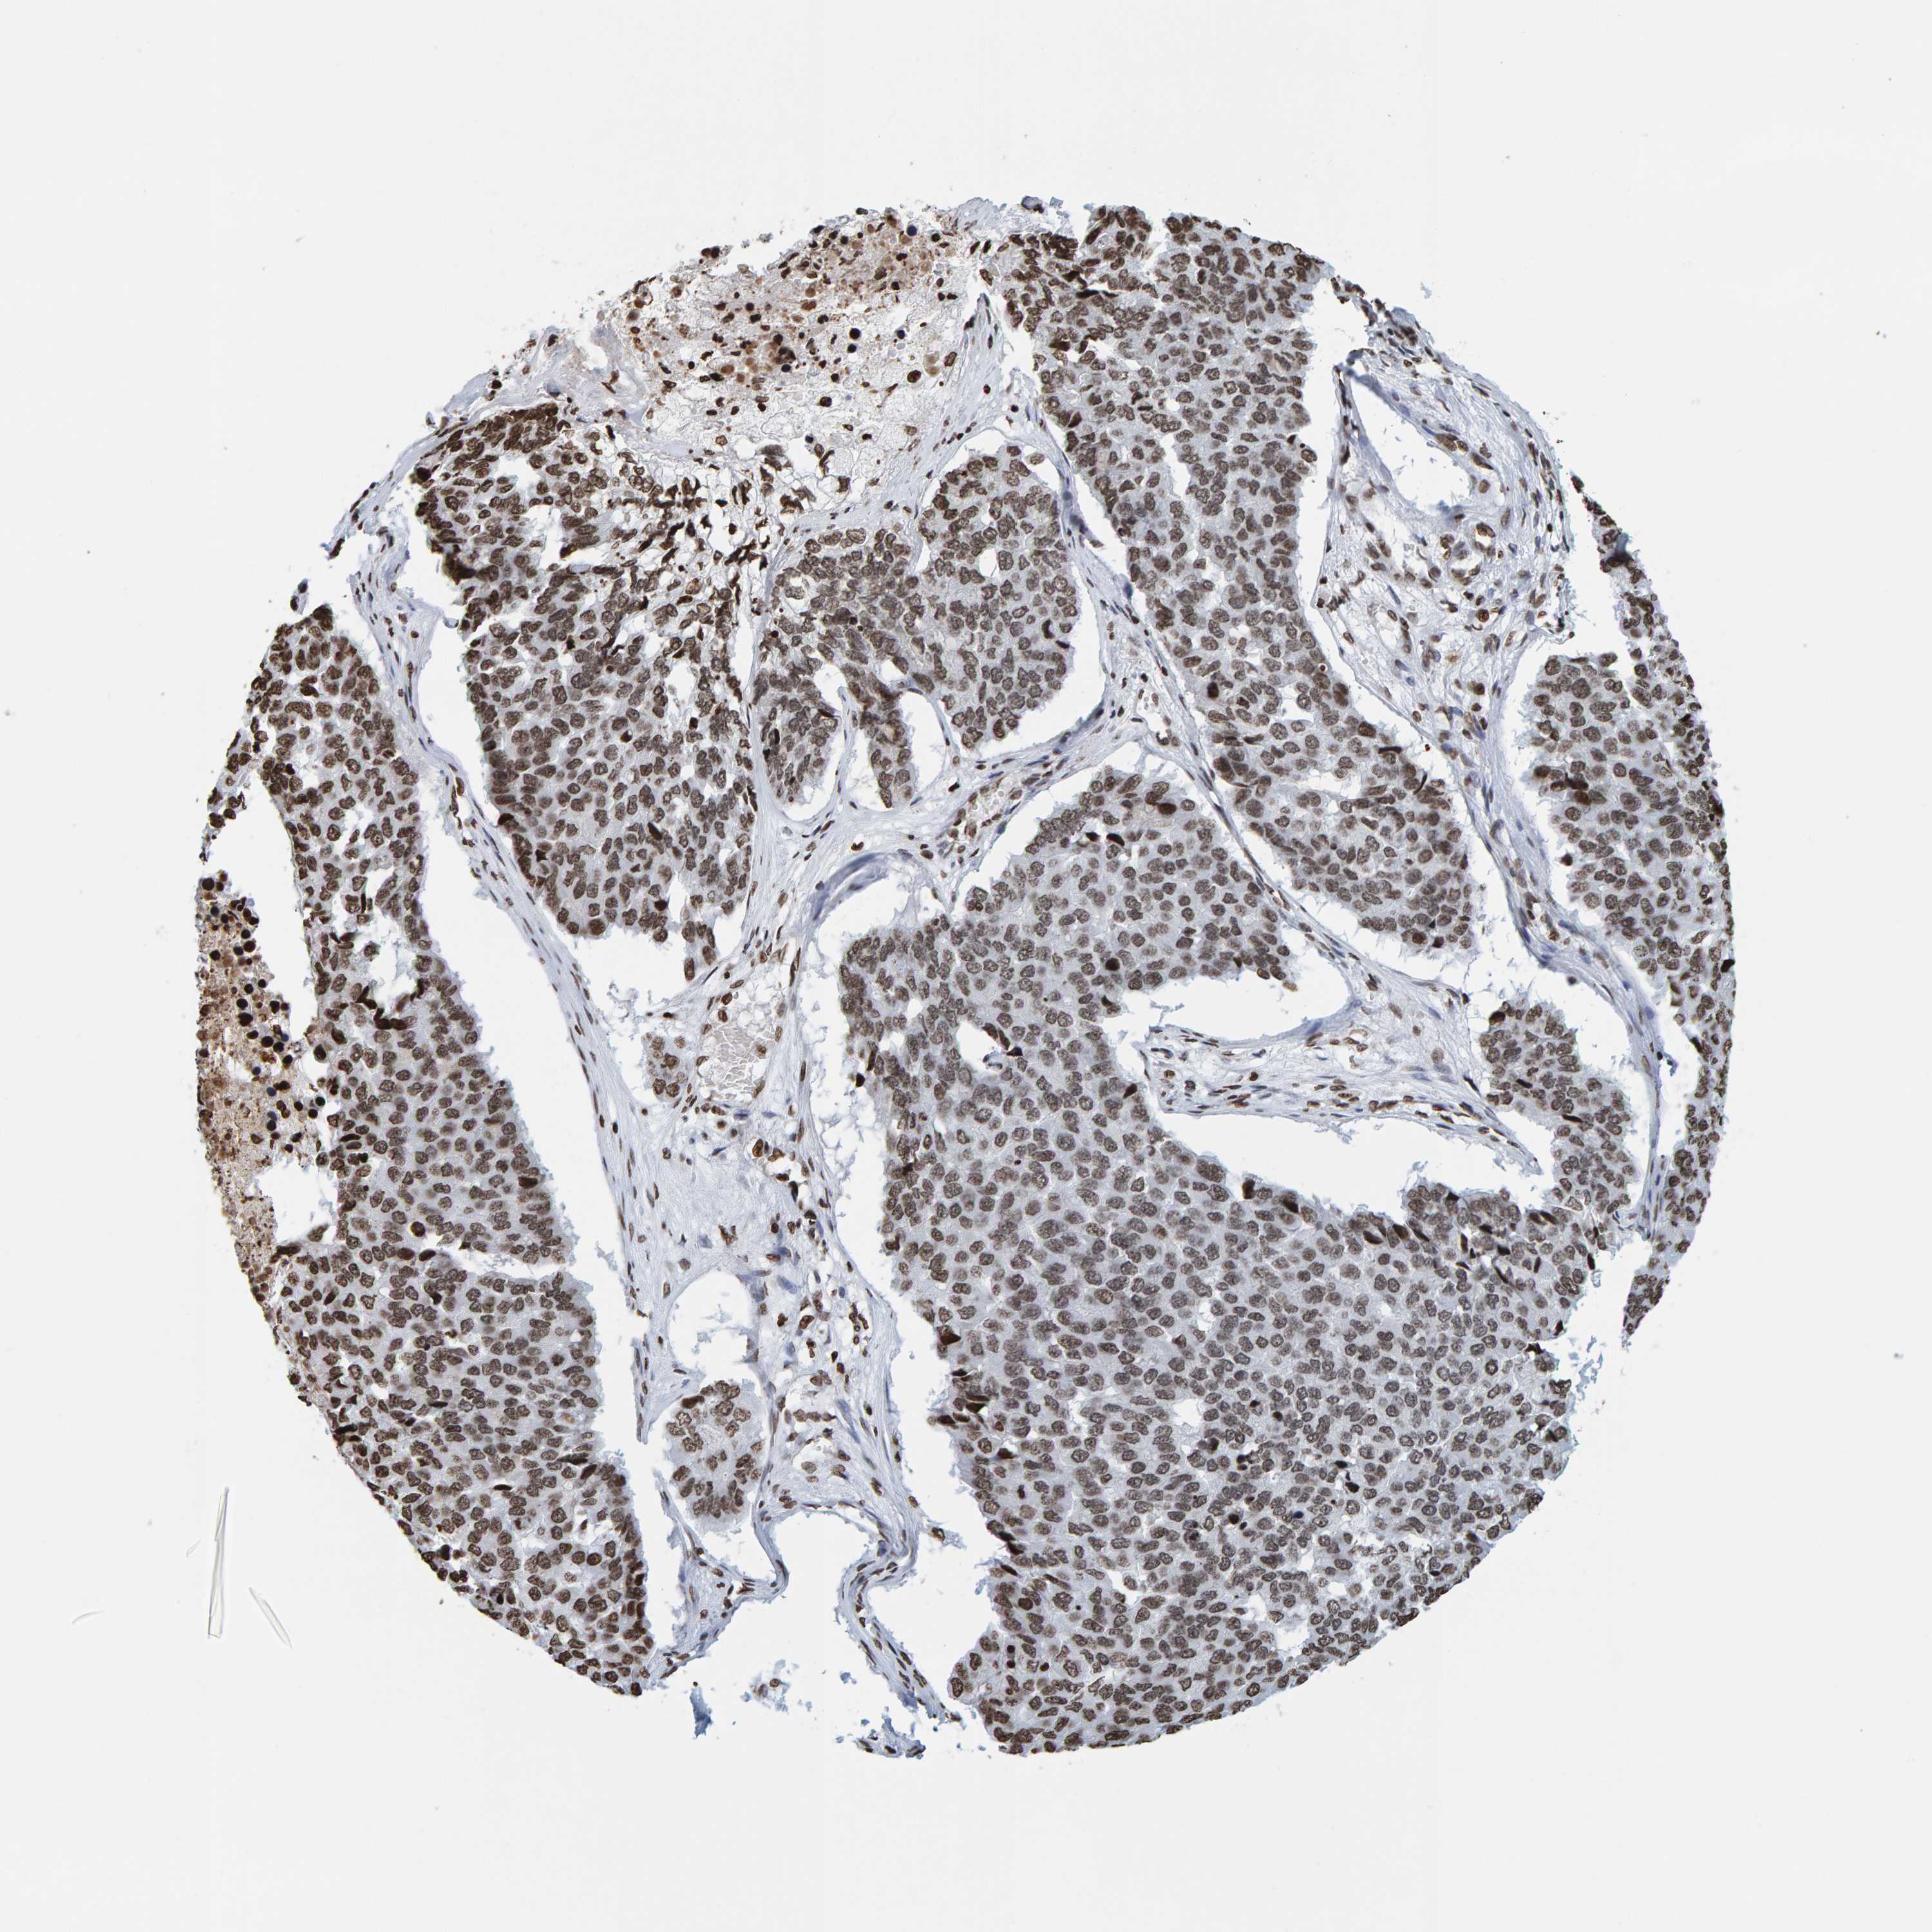

PANCREATIC CANCER - Protein expressioni

A mouse-over function shows sample information and annotation data. Click on an image to view it in a full screen mode. Samples can be filtered based on level of antibody staining by selecting one or several of the following categories: high, medium, low and not detected. The assay and annotation is described here.

Note that samples used for immunohistochemistry by the Human Protein Atlas do not correspond to samples in the TCGA dataset.

Antibody stainingi

Antibody staining in the annotated cell types in the current human tissue is reported as not detected, low, medium, or high, based on conventional immunohistochemistry profiling in selected tissues. This score is based on the combination of the staining intensity and fraction of stained cells.

Each image is clickable and will lead to virtual microscopy that enables deeper exploration of all samples and also displays staining intensity scores, fraction scores and subcellular localization as well as patient and tissue information for each sample.

Antibody HPA023378

Antibody CAB019269

Staining

High

Medium

Low

Not detected

Intensity

Strong

Moderate

Weak

Negative

Quantity

>75%

75%-25%

<25%

None

Location

Nuclear

Cytoplasmic/membranous

Cytoplasmic/membranous,nuclear

Adenocarcinoma, NOS

Adenocarcinoma, metastatic, NOS